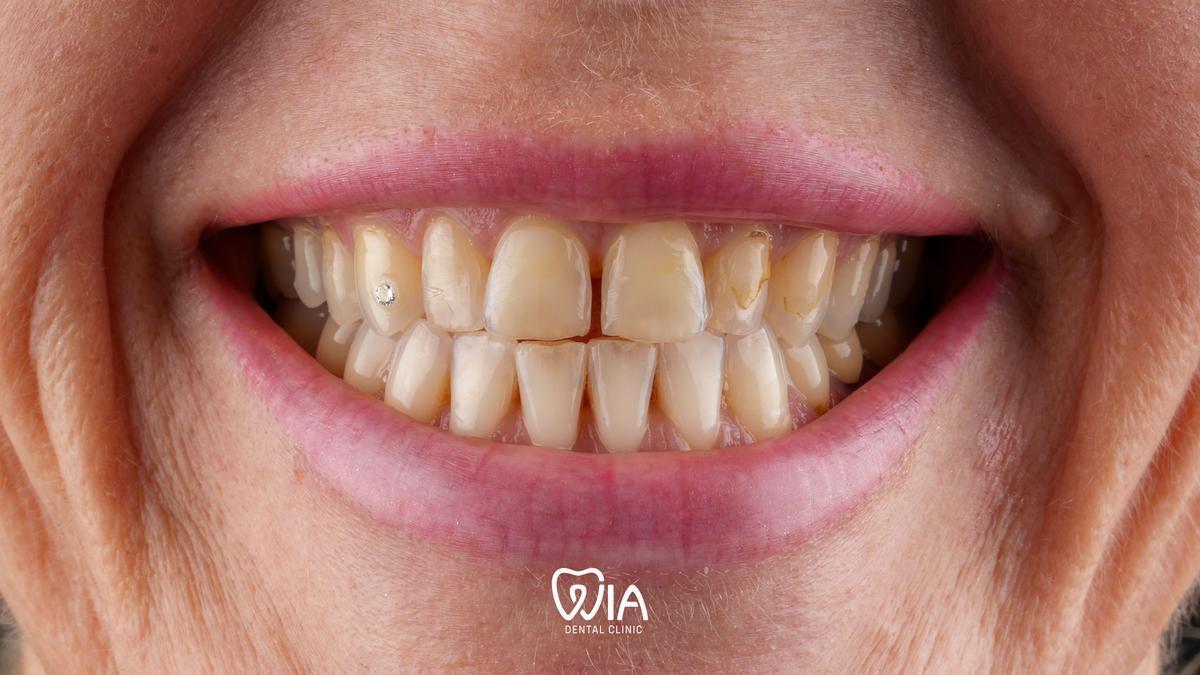

Real stories from real people

E.max Veneers

Real results of our patients